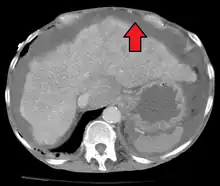

Ultrasound investigation is often done before attempts to remove fluid from the abdomen. This may reveal the size and shape of the abdominal organs, and Doppler studies may show the direction of flow in the portal vein, as well as detecting Budd–Chiari syndrome (thrombosis of the hepatic vein) and portal vein thrombosis. The sonographer also can estimate the amount of ascitic fluid, and difficult-to-drain ascites may be drained under ultrasound guidance. An abdominal CT scan is more accurate than a sonogram to reveal abdominal organ structure and morphology.[12]